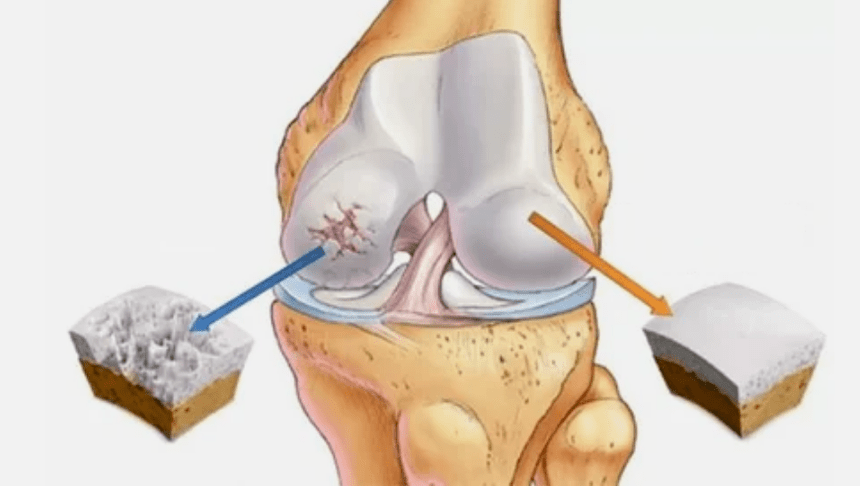

The arthrosis of the joint develops for a long time, initially only affects the hyaline cartilage, then spreads to the bone, includes the synovial shell, muscles and the entire joint capsule.In the first or early stage of arthrosis, the lesion is slightly manifested: minor pain after hard work, swelling, redness of the skin.Due to ignoring unpleasant sensations, the knot is deformed, inflamed, brings severe pain, their roof falls in the morning.The disease is characterized by the disappearance of pain after the development of the joint.If left untreated, a person completely loses the mobility of the joint.

- The primary lesion affects the Hialin cartilage.In case of circulatory disorders, the worsening of pathological power occurs.The first step or cause, which can occur arthritis.

- Pathologies of the hyaline dress.The arrangement of the cartilage leads to the replacement of its pathological tissue - bone structures.

- Anomal growths appear in the cartilage - osteophytes.

- The innate violation of the natural anatomy of the cartilage and bone provokes the overload of healthy cartilage areas.Destruction of articular tissue without treatment is constantly progressing and leading to disability.

When the disease rate increases, the pathological processes are still aggravated.After all, the whole Haali cartilage is destroyed.